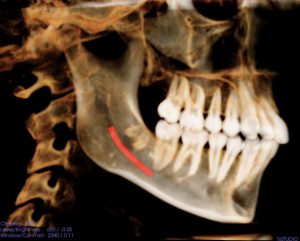

One of the major risks of removing the lower wisdom teeth is injury to the inferior alveolar nerve (IAN). The risk of injury to the IAN ranges from 0.35% to 8.4% during wisdom teeth removal. This causes numbness to the patient’s lip and chin on the side of the injury. In majority of cases, the numbness is temporary and full feeling is regained over weeks to months. For higher risk situations, there is an alternative procedure known as coronectomy or partial odontectomy, which involves removing the crown (top part of the tooth) only and leaving the roots behind. This substantially minimizes the risk of a nerve injury.

The roots that are left behind can migrate over time. However, in only 3% of patients will this impair healing and require a second surgery for its removal. This second surgery is typically safer since the roots migrate away from the nerve.